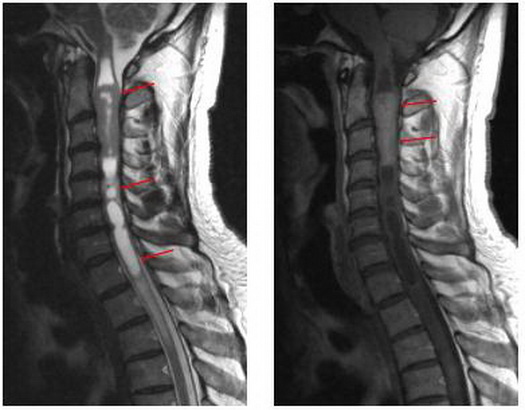

В области шеи грыжи наблюдаются редко, но у многих людей здесь обнаруживают остеофиты, деформирующие края позвонков.

Снимки МРТ шейного отдела позвоночника в коронарной и сагиттальной проекциях

МРТ дает возможность выявить заболевания шейного отдела позвоночника и проверить состояние кровеносных сосудов, непосредственно влияющих на работоспособность головного мозга.

Краниовертебральная область и шейный отдел позвоночника. Показания к использованию метода:

• грыжи межпозвонковых дисков, как проявление остеохондроза, являющиеся наиболее частой причиной болей в шейном отделе позвоночника с возможной иррадиацией в плечевые суставы, верхние конечности и голову;

• крупные грыжи дисков, оказывающие давление на спинной мог и нервные корешки, а также вызывающие ишемическое их поражение, что в свою очередь приводит к нарушениям чувствительности и двигательной функции верхних конечностей;